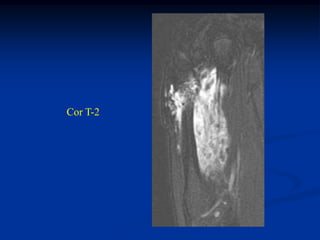

Case #1199

30 year male with

myxoid liposarcoma

posterior thigh

Sagittal T-1 MRI

Sagittal T-2 MRI

tumor

Axial T-1 MRI

Axial Gad contrast MRI

Coronal Gad

contrast MRI